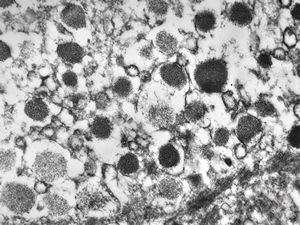

F,68y. | APUD carcinoma

F,68y. | APUD carcinoma

F,68y. | APUD carcinoma

F,68y. | APUD carcinoma

F,68y. | APUD carcinoma (Bodian siver impregnation)